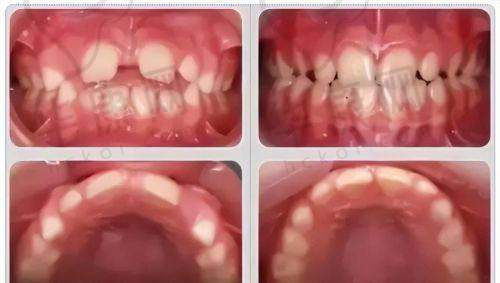

曾经有一位小朋友,牙齿存在明显的地包天问题,家长非常担心会影响孩子的面部发育和自信心。来到株洲荷塘唯美口腔后,医生为他进行了详细的检查和评估,制定了个性化的早期矫正方案。在矫正过程中,医生和护士给予了孩子充分的关心和鼓励,让孩子能够积极配合治疗。经过一段时间的矫正,孩子的地包天问题得到了明显改善,面部外观也更加美观。家长对矫正成效非常满意,也对医院的专精服务和技术水平赞不绝口。